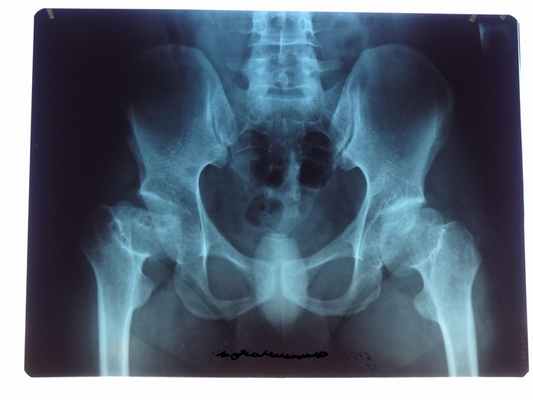

Рентген проводится в любом случае. Однако видимые изменения в суставе можно установить лишь на прогрессирующей стадии болезни. Одним из главных сигналов Болезни Альбека на рентгенограмме является склерозирование - болезненное уплотнение костной ткани, которое возникает посредством перенагрузки коленного сустава.

На первой стадии болезни структура костной ткани изменена в незначительной степени, тазобедренный сустав сохраняет свои функции, боли отмечаются периодические.

Вторая стадия сопряжена с образованием трещин на поверхности головки тазобедренного сустава. Наблюдаются ограничения в подвижности и постоянные боли.

Третья стадия — вторичный артроз, в патологический процесс вовлечена вертлужная впадина. В значительной степени снижена подвижность сустава. Этой стадии характерны постоянные и сильные боли. Разрушение головки бедренной кости, постоянные боли, атрофия мышц бедра и ягодиц, минимальная подвижность тазобедренного сустава — признаки, свидетельствующие о четвертой, самой тяжелой стадии развития некроза.

Асептический некроз головки бедренной кости

Головка бедренной кости относится к проблемным зонам, в которых часто возникает закупорка артерий, накопительные повреждения из-за перегрузок и бытовых травм, сложные травмы тазобедренного сустава (переломом головки бедренной кости). Различные патологические процессы могут привести к асептическому некрозу головки бедренной кости.

В большинстве случаев ортопедический прогноз неутешителен, наблюдается тяжелый деформирующий артроз тазобедренного сустава, при котором зачастую применяется эндопротезирование, артродез сустава или корригирующие остеотомии. Ранняя диагностика при помощи магнитно-резонансной томографии (МРТ) тазобедренного сустава позволяет вовремя выявить начало заболевания и порой даже консервативное лечение даёт отличные результаты, исключая хирургическое вмешательство.